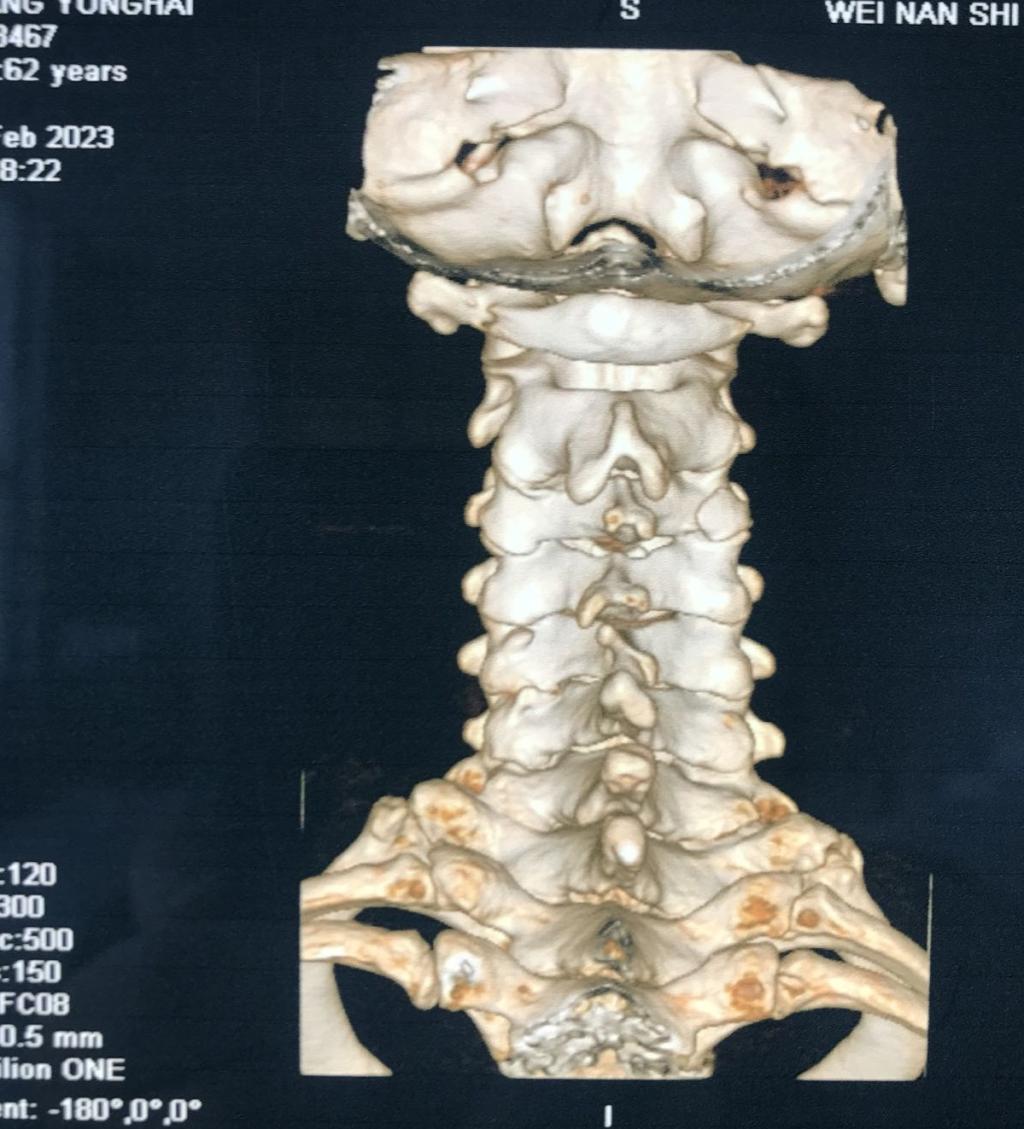

近日,一位颈部外伤合并肢体瘫痪症状患者来到MILAN.COM骨一科就诊。经入院后紧急检查,发现患者为颈3.4椎体骨折、脱位,并有右后侧关节突关节骨折、绞索,四肢肌力约3级。

入院后,科室立即进行常规术前检查,给予8公斤大重量颈枕带牵引,但因关节脱位的绞索,颈椎复位困难。几日后,患者在牵引过程中出现右上肢抽痛加重,肌力减低表现。紧急时刻,骨一科决定立即为患者行急诊手术治疗。

经过有序准备,为患者先行颈后路减压,解锁关节突绞索,牵引复位,使用颈椎侧块螺钉固定,同时椎板间植骨融合。随后再将患者转为仰卧位,再行颈前路脱位椎体的间盘摘除,融合器植入,钢板螺钉固定,历时3小时,顺利结束。患者术后恢复良好,肢体功能状态较术前改善显著,上肢抽痛症状消失,肌力已达4-5级,患者及家属对治疗效果颇为满意。